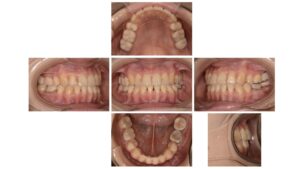

After

| 主訴 | 歯並びを治したい |

| 診断名 | 叢生(混雑した歯並び) |

| 年齢・性別 | 30歳 女性 |

| 治療期間・回数 | 24ヶ月、20回 |

| 治療方法 | 上下顎左右第一小臼歯を抜歯し、マルチブラケット装置 |

| 費用 | 検査料 55,000円 基本矯正料 990,000円 処置料 5,500円 / 月 |

| デメリット・注意点 | 唇に装置が当たって口内炎になる可能性 歯根吸収の可能性 調整のたびに2〜3日程度、上下の歯が接すると痛みが生じる |

| 備考 | 歯列が小さく、骨格内に歯を並べていくために上下左右の小臼歯を抜歯して治療を行なっています。 噛み合わせと歯並びが改善したことで、快適な食生活を送ることができたと喜んでいただいています。 歯を抜いた方がよいのか、抜かなくても改善できるのかは、患者さんの骨格や歯の大きさによりますので、個人差が大きいです。 矯正相談は初回は無料でうかがいますので、お気軽にご連絡ください☎️ 目白駅より徒歩4分の歯医者さん 目白ヶ丘デンタルクリニック・矯正歯科 |